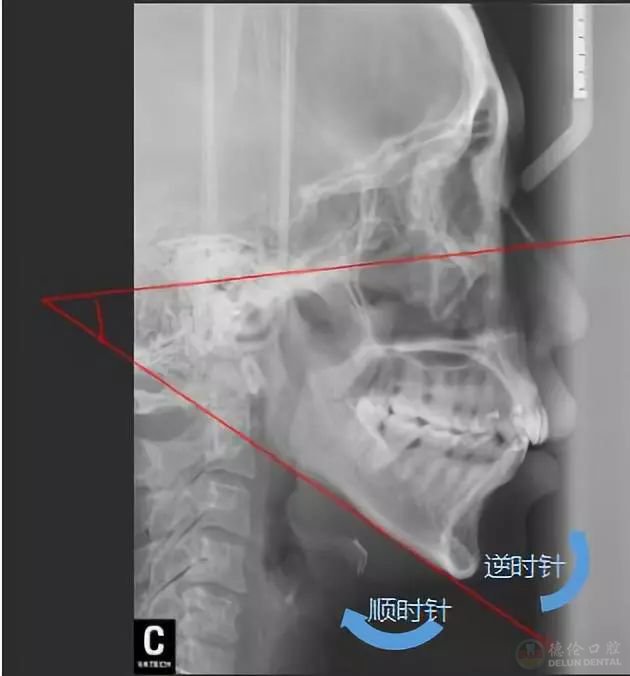

▲颌平面的逆时针旋转,即是下巴往前翘

▲获奖病例侧貌X线前后对比

“按照常规方案,这种情况是不太适合推磨牙远移,因为推磨牙远移会造成整个颌平面的顺时针旋转,就会出现面型更不好看。但是因为给她设计了压低、另外打了支抗钉来控制它的矢状向和垂直向,就没有出现顺时针旋转,反而出现了整个颌平面的逆时针旋转,下巴还变好看了。”